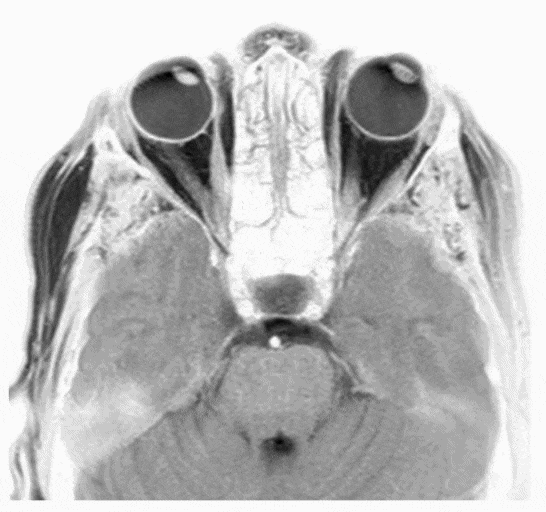

Magnetic resonance-based eye tracking using deep neural networks

M Frey, M Nau, CF Doeller

After lots of discussions in our lab meetings about the problems with eye-trackers we decided to build a deep learning framework that decodes eye position directly from MRI data.

Nature neuroscience (2021)